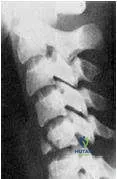

What type of fracture is presented in the radiograph (Slide):

Correct Answer: Teardrop fracture

Clearly seen in this radiograph is a fracture along the anterior/inferior vertebral body, which is a characteristic of a teardrop fracture.